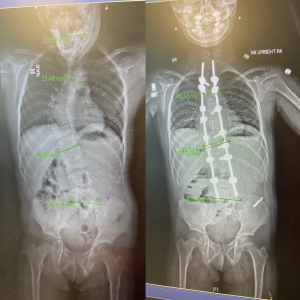

The surgery approach that Dr. Albert outlined for Talley and her family involved a Shilla implant combined with a spinal fusion. There would be no need for multiple surgeries to correct her curve, Dr. Albert could do it in one.

The four-hour surgery involved a spinal fusion and placing a Shilla implant along Talley’s spine, which acted as a track system that will grow and expand as she matures. This approach allowed Talley to preserve her growth, something that was important to Talley because of her small stature.

Since her spine surgery, it’s safe to say that Talley is thriving. Two years later, she has grown almost 5 inches and loves to sing karaoke and hang out with her friends.